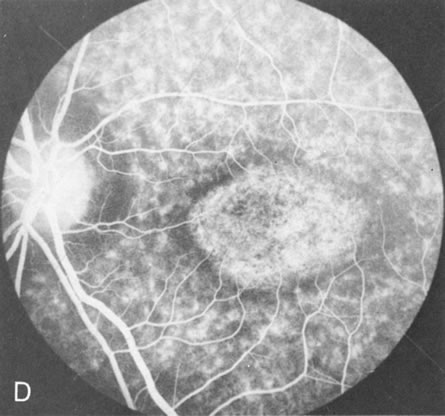

Fig. 1. Retinitis pigmentosa. A. A typical area of bone spicule pigmentation. B. Diffuse dye leakage is apparent throughout the posterior pole. C. The early angiogram shows dilated and irregular retinal radial peripapillary capillaries and perifoveal retinal capillaries. D. Leakage from these vessels are evident in the late angiogram.

Of more clinical importance is the role of FA in the diagnosis and treatment of cystoid macular edema (CME) (Fig. 1C and D). Stereoscopic FA indicates that the leakage, which may be diffuse or have the typical petaloid stellate appearance of CME, can come from the perifoveal retinal capillaries, from the choroid through the RPE, or from a combination of both sources.4 With the recent suggestion that CME in RP may be successfully treated with acetazolamide,5, 6 FA is thus important to document the diagnosis of CME, establish the origin(s) of leakage, and follow patients during and after therapy.